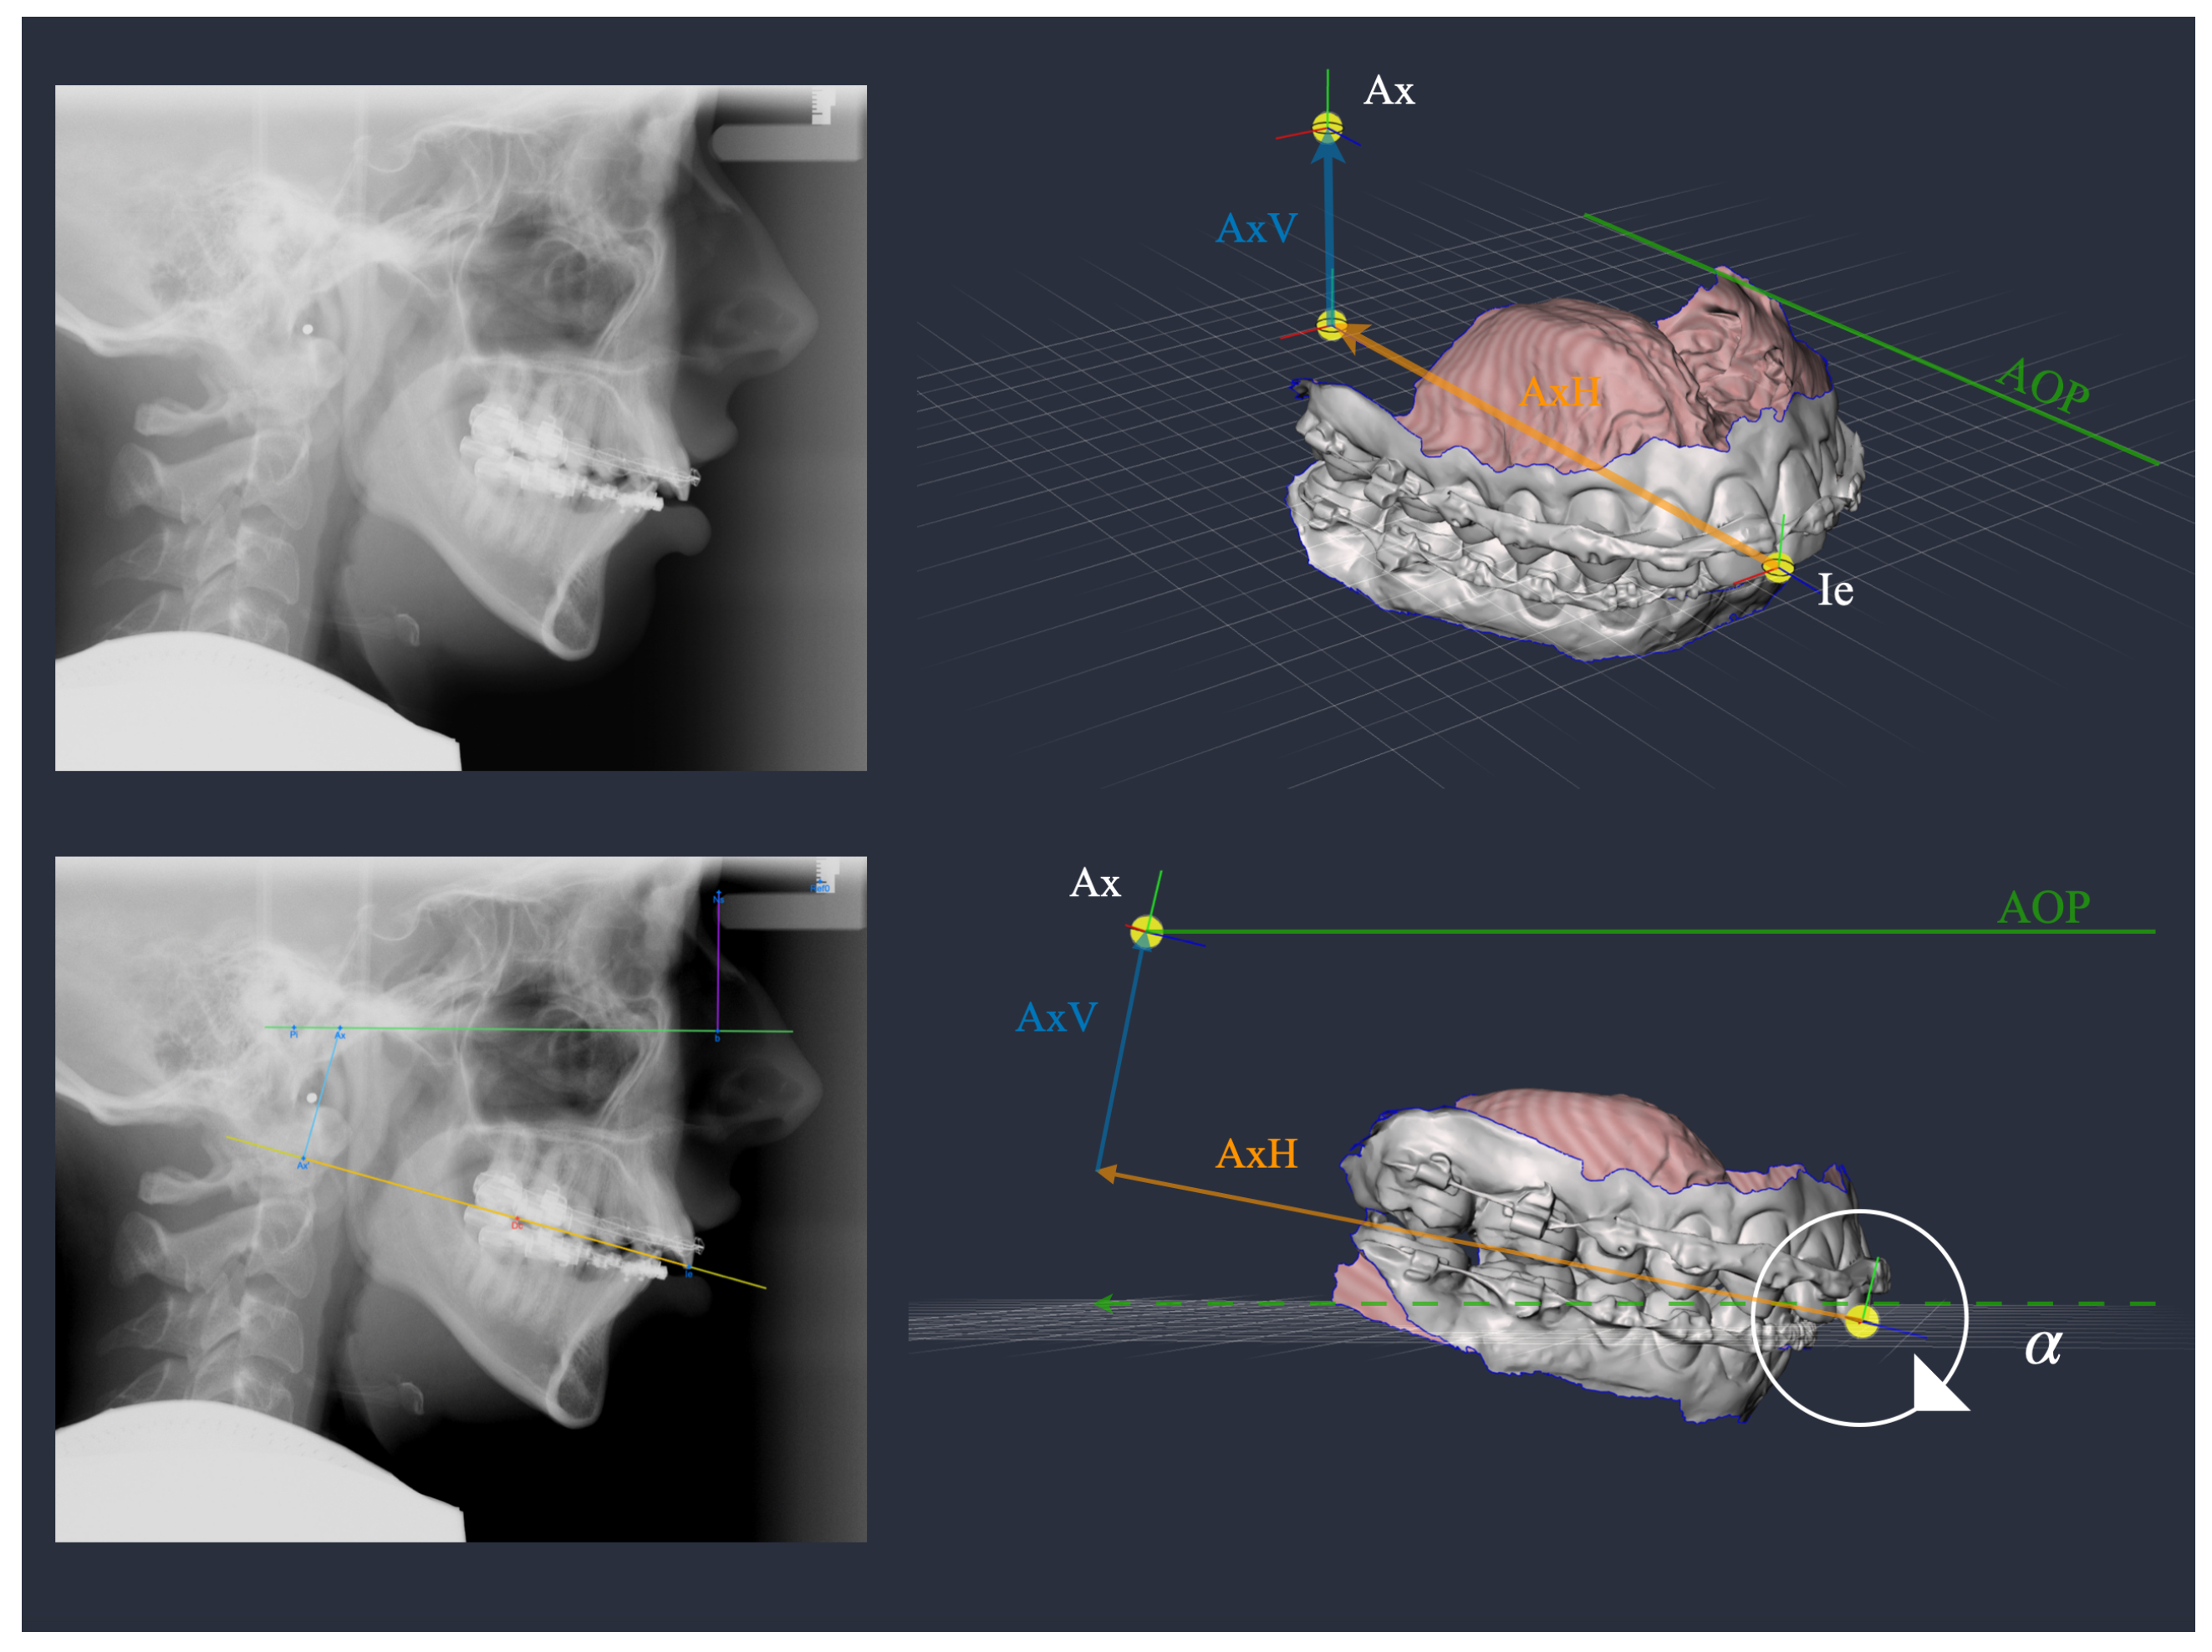

| 323 | 7.6 | 5.3 | 191 | 6.5 | 5.0 | ||

| AxV | 323 | 30.2 | 5.7 | 191 | 35.8 | 5.7 | <0.001 |

| AxH | 323 | 88.0 | 6.7 | 191 | 93.1 | 8.1 | <0.001 |

| 128 | 7.8 | 3.4 | 204 | 11.1 | 3.3 | 182 | 2.4 | 4.0 | <0.001 | ||

| AxV | 128 | 36.2 | 4.6 | 204 | 26.5 | 3.8 | 182 | 35.9 | 4.5 | <0.001 1 | |

| AxH | 128 | 98.9 | 5.5 | 204 | 88.1 | 5.4 | 182 | 85.6 | 5.6 | <0.001 | |